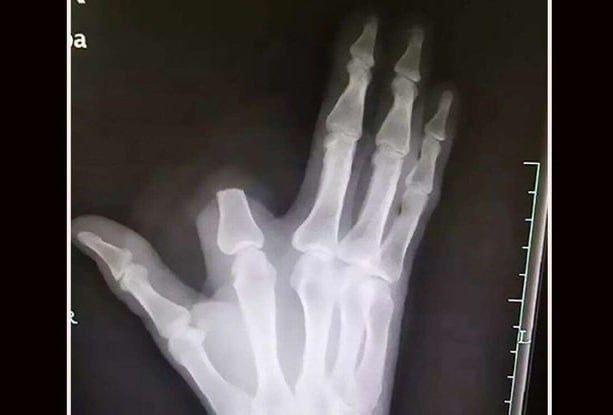

В провинции Чжэцзян, Китай, 60-летний фермер, работая в поле, был укушен змеёй. В панике мужчина решил, что змея ядовита, и самостоятельно ампутировал себе указательный палец подручными средствами.

После процедуры фермер перевязал рану и самостоятельно добрался до больницы. Однако врачи сообщили, что змея была неядовитой, и ампутация не требовалась. Палец спасти не удалось, так как он остался на месте происшествия.